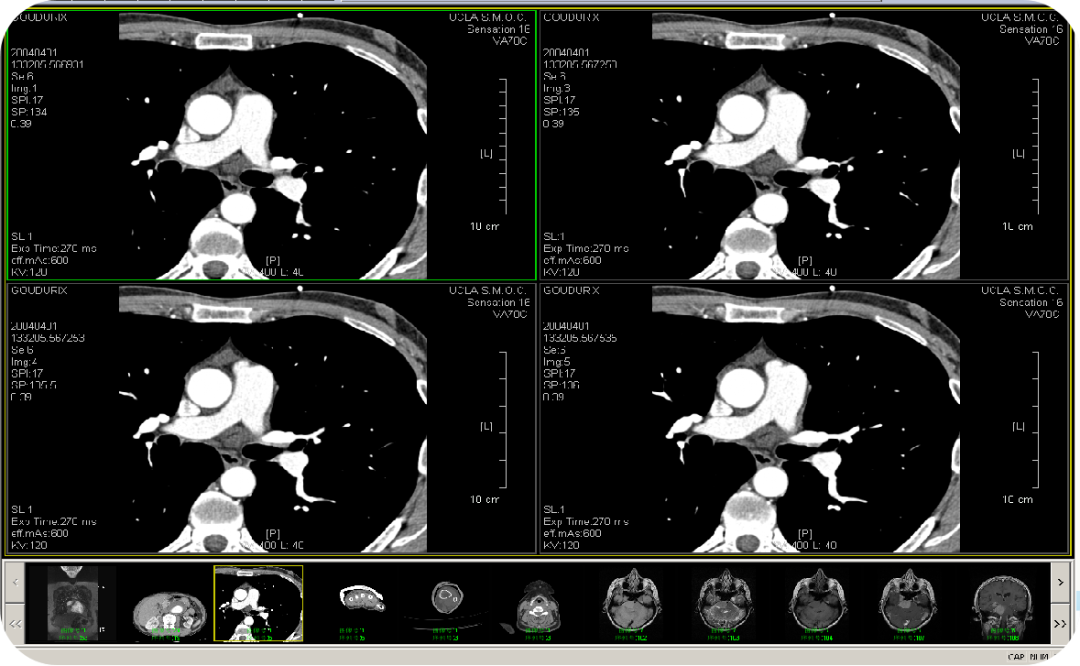

• CT/MR三维后处理功能(选配)

图片